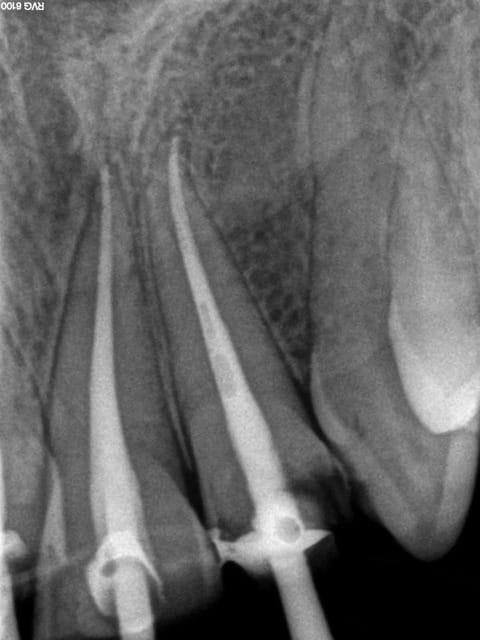

Cas concret ...... en cours pause après 3/4 d'heure. taille à suivre, c'est là ou je chie, ca manque de finesse ! -)))))

Noter le repositionnement des cones , en 2 % c'est impossible.